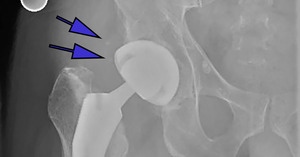

A manual medical record review was conducted by three upper level residents (PK, RD, SY) to investigate if administration of a NSAID was administered during the hospital stay; specifically, both drug type and dose were recorded. DVT prophylaxis, specifically the dose of ASA, was also recorded. Finally, HO was conducted by one senior resident (first author PK), using the Brooker Classification System.18 (Figures 1a-1c) Observing this system, Class 1 is described as islands of bone within the soft tissues about the hip. Class 2 includes bone spurs originating from the pelvis or proximal end of the femur, leaving at least 1 cm. between opposing bone surfaces. Class 3 consists of bone spurs originating from the pelvis or proximal end of the femur, reducing the space between opposing bone surfaces to less than 1 cm. Class 4 shows apparent bone ankylosis of the hip.19 Finally, if post-operative complications such as dislocation occurred this was included in our review of the EMR.